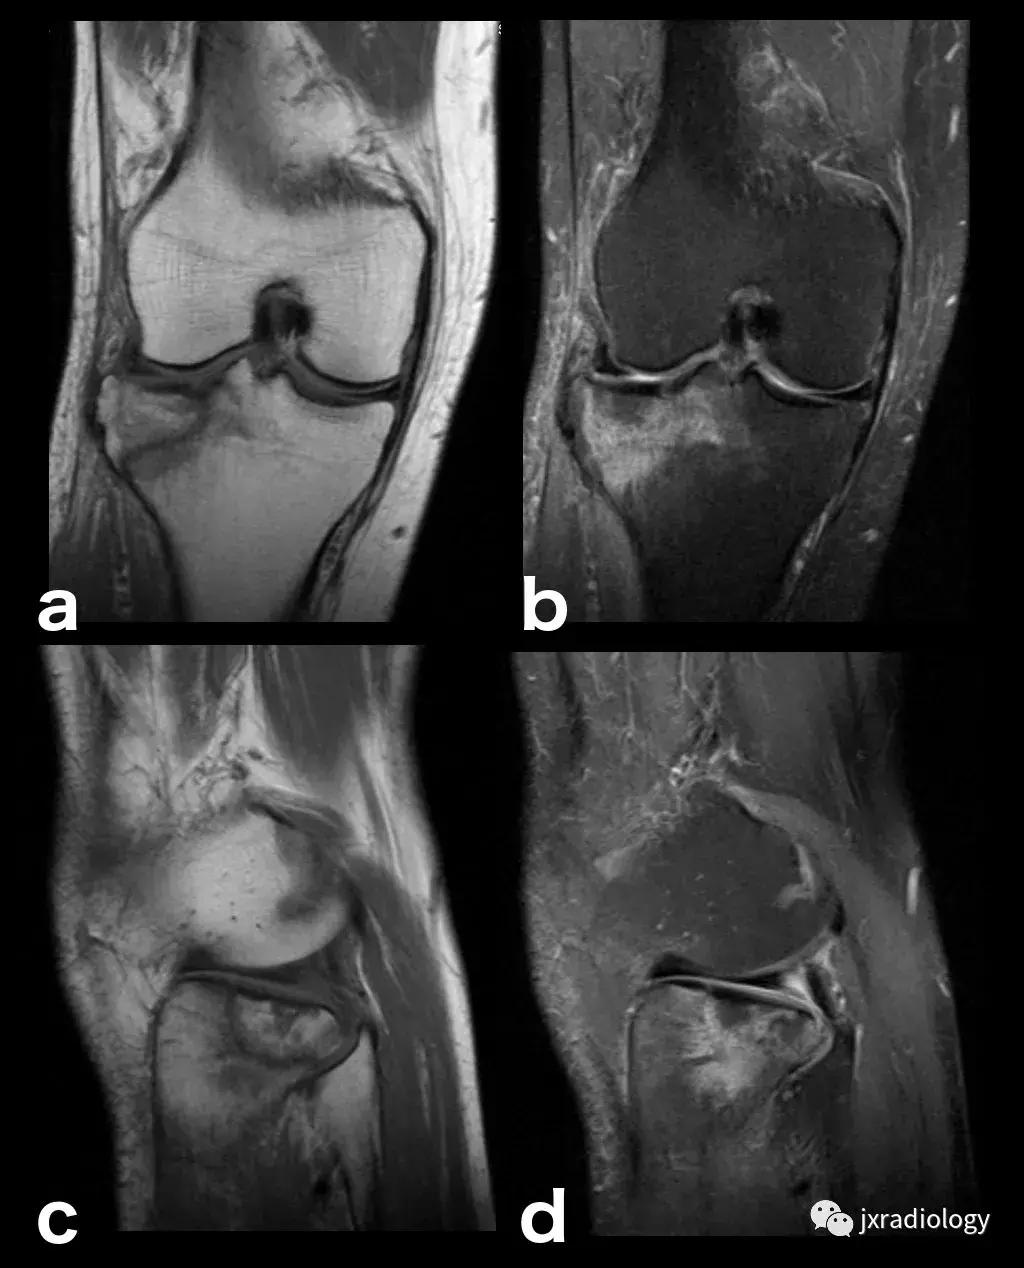

图25:短暂性骨髓水肿综合征(短暂性骨质疏松症):30岁女性急性膝部疼痛的矢状位FS-PDWI MR影像显示骨髓水肿,涉及非负重区域股骨外侧髁骨髓水肿在1年内几乎完全自发消退。短暂性骨髓水肿综合征是自限性病变,其表现为与MRI研究中的骨髓水肿证据相关的关节痛。其病因仍不确定。

图26:局限性游走性骨质疏松症(具有位置变化的短暂性骨髓水肿综合征)(连续冠状PD-FS-WI):在一些情况下,在连续MRI上看到骨髓水肿的位置变化,这被称为局限性游走性骨质疏松症(RMO);尽管可以自愈的短暂性骨髓水肿综合征的情况更为常见,但可以在一小部分病例中转移到不同的关节,或者(甚至更罕见)转移到同一关节内的不同部位(关节内转移) ,如关于该患者所见。在这个关节内RMO病例中,没有创伤史,水肿始于股骨内侧髁,3个月后发现转移到外侧髁。

图27:废用性骨质疏松症(DO):在骨骺上的所有序列中显示的融合和斑片状中-高信号影是典型的长期固定后的短暂性骨质疏松症。恢复活动在废用骨中产生比在正常骨中更大的应力,因为必须支撑负载的骨小梁更小更弱,因此出现骨髓水肿(应力反应也在内侧髁上看到并用* 标识)。一个愈合的外侧胫骨平台骨折(箭头)。(a-e:PD-FS-WI; f:T1-WI)。值得注意的是,复杂性局部疼痛综合征(CRPS,包括包括反射*交性**感神经营养不良,痛觉神经营养不良和Sudeck骨萎缩)具有与DO相同的MRI骨水肿模式,但其病理生理学与废用脱钙无关,并且总是伴有疼痛(DO是无症状患者的偶然发现,在有外固定的患者中)。